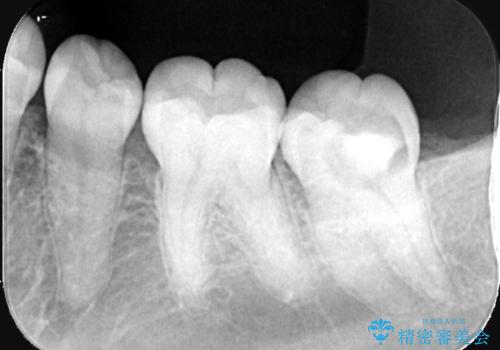

- 昨日からのズキズキとした激しい痛みを主訴にご来院されました。レントゲンおよび歯髄診察の結果、不可逆性の歯髄炎(歯の神経の重度の炎症)と診断。歯を残すことを第一に、まず痛みの原因である神経を取り除く根管治療を提案しました。また、虫歯が歯肉の下まで深く進行していたため、根管治療後に歯周外科処置を行い、最終的に精密なセラミッククラウンで修復する、総合的な治療計画を立案しました。

治療はまず、根管治療から始め、感染した神経を徹底的に除去することで、痛みをすぐに解消しました。再発を防ぐため、ラバーダムや顕微鏡を使って、根管内を丁寧に、そして精密に処置しました。次に、深い部分の虫歯を確実に治療するため、歯周外科処置を行い、治療しやすい環境を整えました。最後に、機能と見た目に優れたセラミッククラウンを作製・装着。根管治療から外科処置、審美修復までを一貫して行うことで、再発リスクの低い、長期的に安定して使える奥歯を取り戻していただけました。